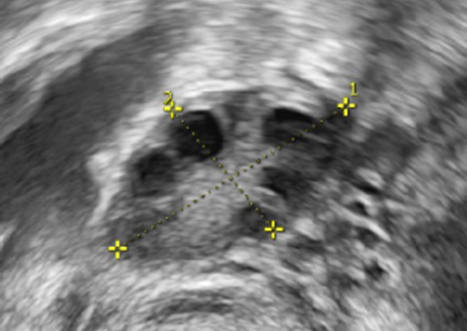

Unauffällige oviarielle Reserve, AFC 8

Reduzierte ovarielle Reserve, AFC 2

AFC erhöht bei PCOS, ACF > 15